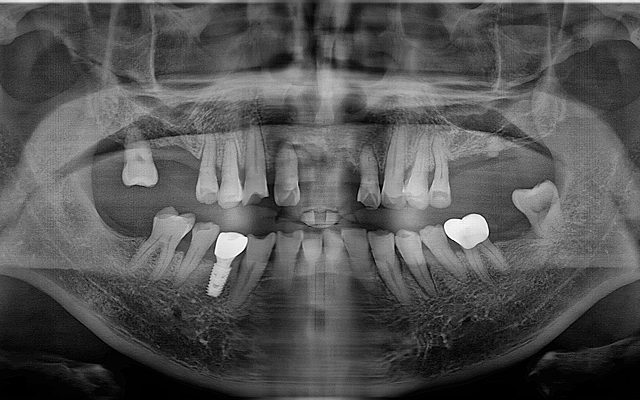

전악 케이스

- 상·하악 전체 보철 설계를 통해 정확한 교합(물림) 회복

- 심미·발음·저작 기능을 종합 고려한 자연스러운 전악 임플란트

고난도 뼈이식 케이스

- 정밀 영상 진단으로 결손 부위를 파악하여 안전하게 골이식

- 미세 수술 장비를 활용해 식립 안정성 및 성공률 향상